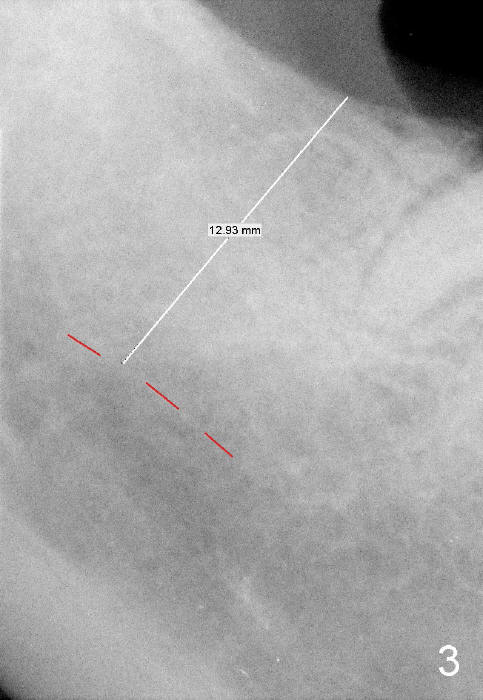

A 57-year-old lady returns for #31 implantation. The vertical edentulous space is limited, as the opposing tooth is supraerupted (Fig.1 arrow). Preop PA is critical (Fig.2), since it is used to measure the bone height (Fig.3: 12 mm). The length of the implant is expected to be 10 mm. The initial osteotomy depth is 8 mm (Fig.4); it appears that the trajectory should be adjusted. Osteotomy increases following depth and angulation adjustment (Fig.5: 4.5x10 mm drill). The submerged implant (5.3x10 mm) is placed with insertion torque approximately 35 Ncm (Fig.6). The buccal microthreads are exposed (Fig.7); to prepare for bone graft, the buccal plate is decorticated. Following placement of freeze dry mineralized allograft, collagen membrane is fixated by a healing screw (Fig.8). The incision is closed by 4-0 Chromic gut sutures and perio glue (Fig.9).

Bone-level implants offer two options after placement (stages 1 and 2). If the insertion torque is high and there is sufficient vertical edentulous space, a healing abutment is placed (stage 1). No surgery is required for restoration. Otherwise, the implant should be buried, as shown in this case. Two mini-implants are going to be placed to intrude the opposing supraerupted tooth. In fact, the orthodontic intrusion is quite difficult. Finally the intrusion apparatus has to be removed prior to chemotherapy for breast cancer. PAs taken 1 year 3 months (Fig.10) and 1 year 9 months (Fig.11, 6 months post cementation) postop appear to show that there is coronal bone loss. An abutment with short cuff (Fig.11 *) is chosen for final crown (C). Ideally the implant should have been placed deeper (Fig.7) for easy restoration. Pre-op examination and diagnosis are critical.